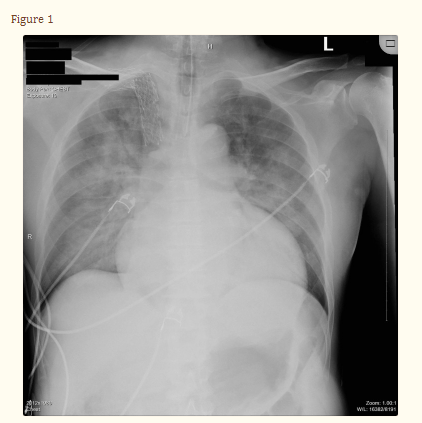

在机械通气的第8天,患出现38.5℃的发热和分泌物增加。检查发现白细胞增多和CXR右上叶新的浸润(图3)。对患者行经皮气管切开术和支气管镜检查。在右肺上叶灌洗的支气管镜检查中,发现他有粘稠的黄褐色分泌物,带有明显的恶臭气味。BAL收集结果发现腐败希瓦氏菌。进行了培养敏感性试验(表1),之后患者开始接受头孢吡肟治疗,并完成了为期10天的抗生素疗程,其临床状况得到了显著改善。出院时患者情况稳定。

图3 胸部X光显示右肺上叶后段有新的浸润